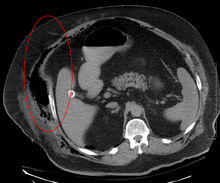

Necrotising fasciitis producing gas in the soft tissues

Early diagnosis is difficult as the disease often looks early on like a simple superficial skin infection.[4] While a number of laboratory and imaging modalities can raise the suspicion for necrotizing fasciitis, the gold standard for diagnosis is surgical exploration in the setting of high suspicion. When in doubt, a small "keyhole" incision can be made into the affected tissue, and if a finger easily separates the tissue along the fascial plane, the diagnosis is confirmed and an extensive debridement should be performed.[2]

Computed tomography (CT scan) is able to detect about 80% of cases while MRI may pick up slightly more.[13]